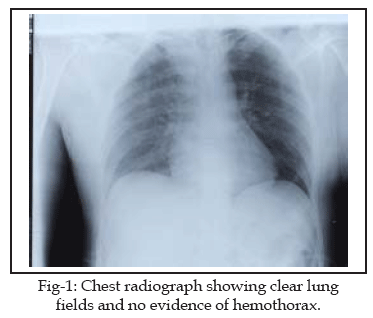

This-32-year old man was brought to the emergency department of our hospital having sustained multiple stab wounds over the anterior aspect of the right chest wall and extremities. On admission his blood pressure was 90/60 mmHg, with a pulse of 80 beats per minute and respiratory rate of 18 per minute. He was hemodynamically stable. His breath sounds were equal bilaterally, without rhonchi or rales. The heart sounds were regular, and, there were no murmurs, rubs, or gallops. Chest radiograph taken on admission did not show any marked abnormality (Fig-1). The emergency routine laboratory investigations were normal.